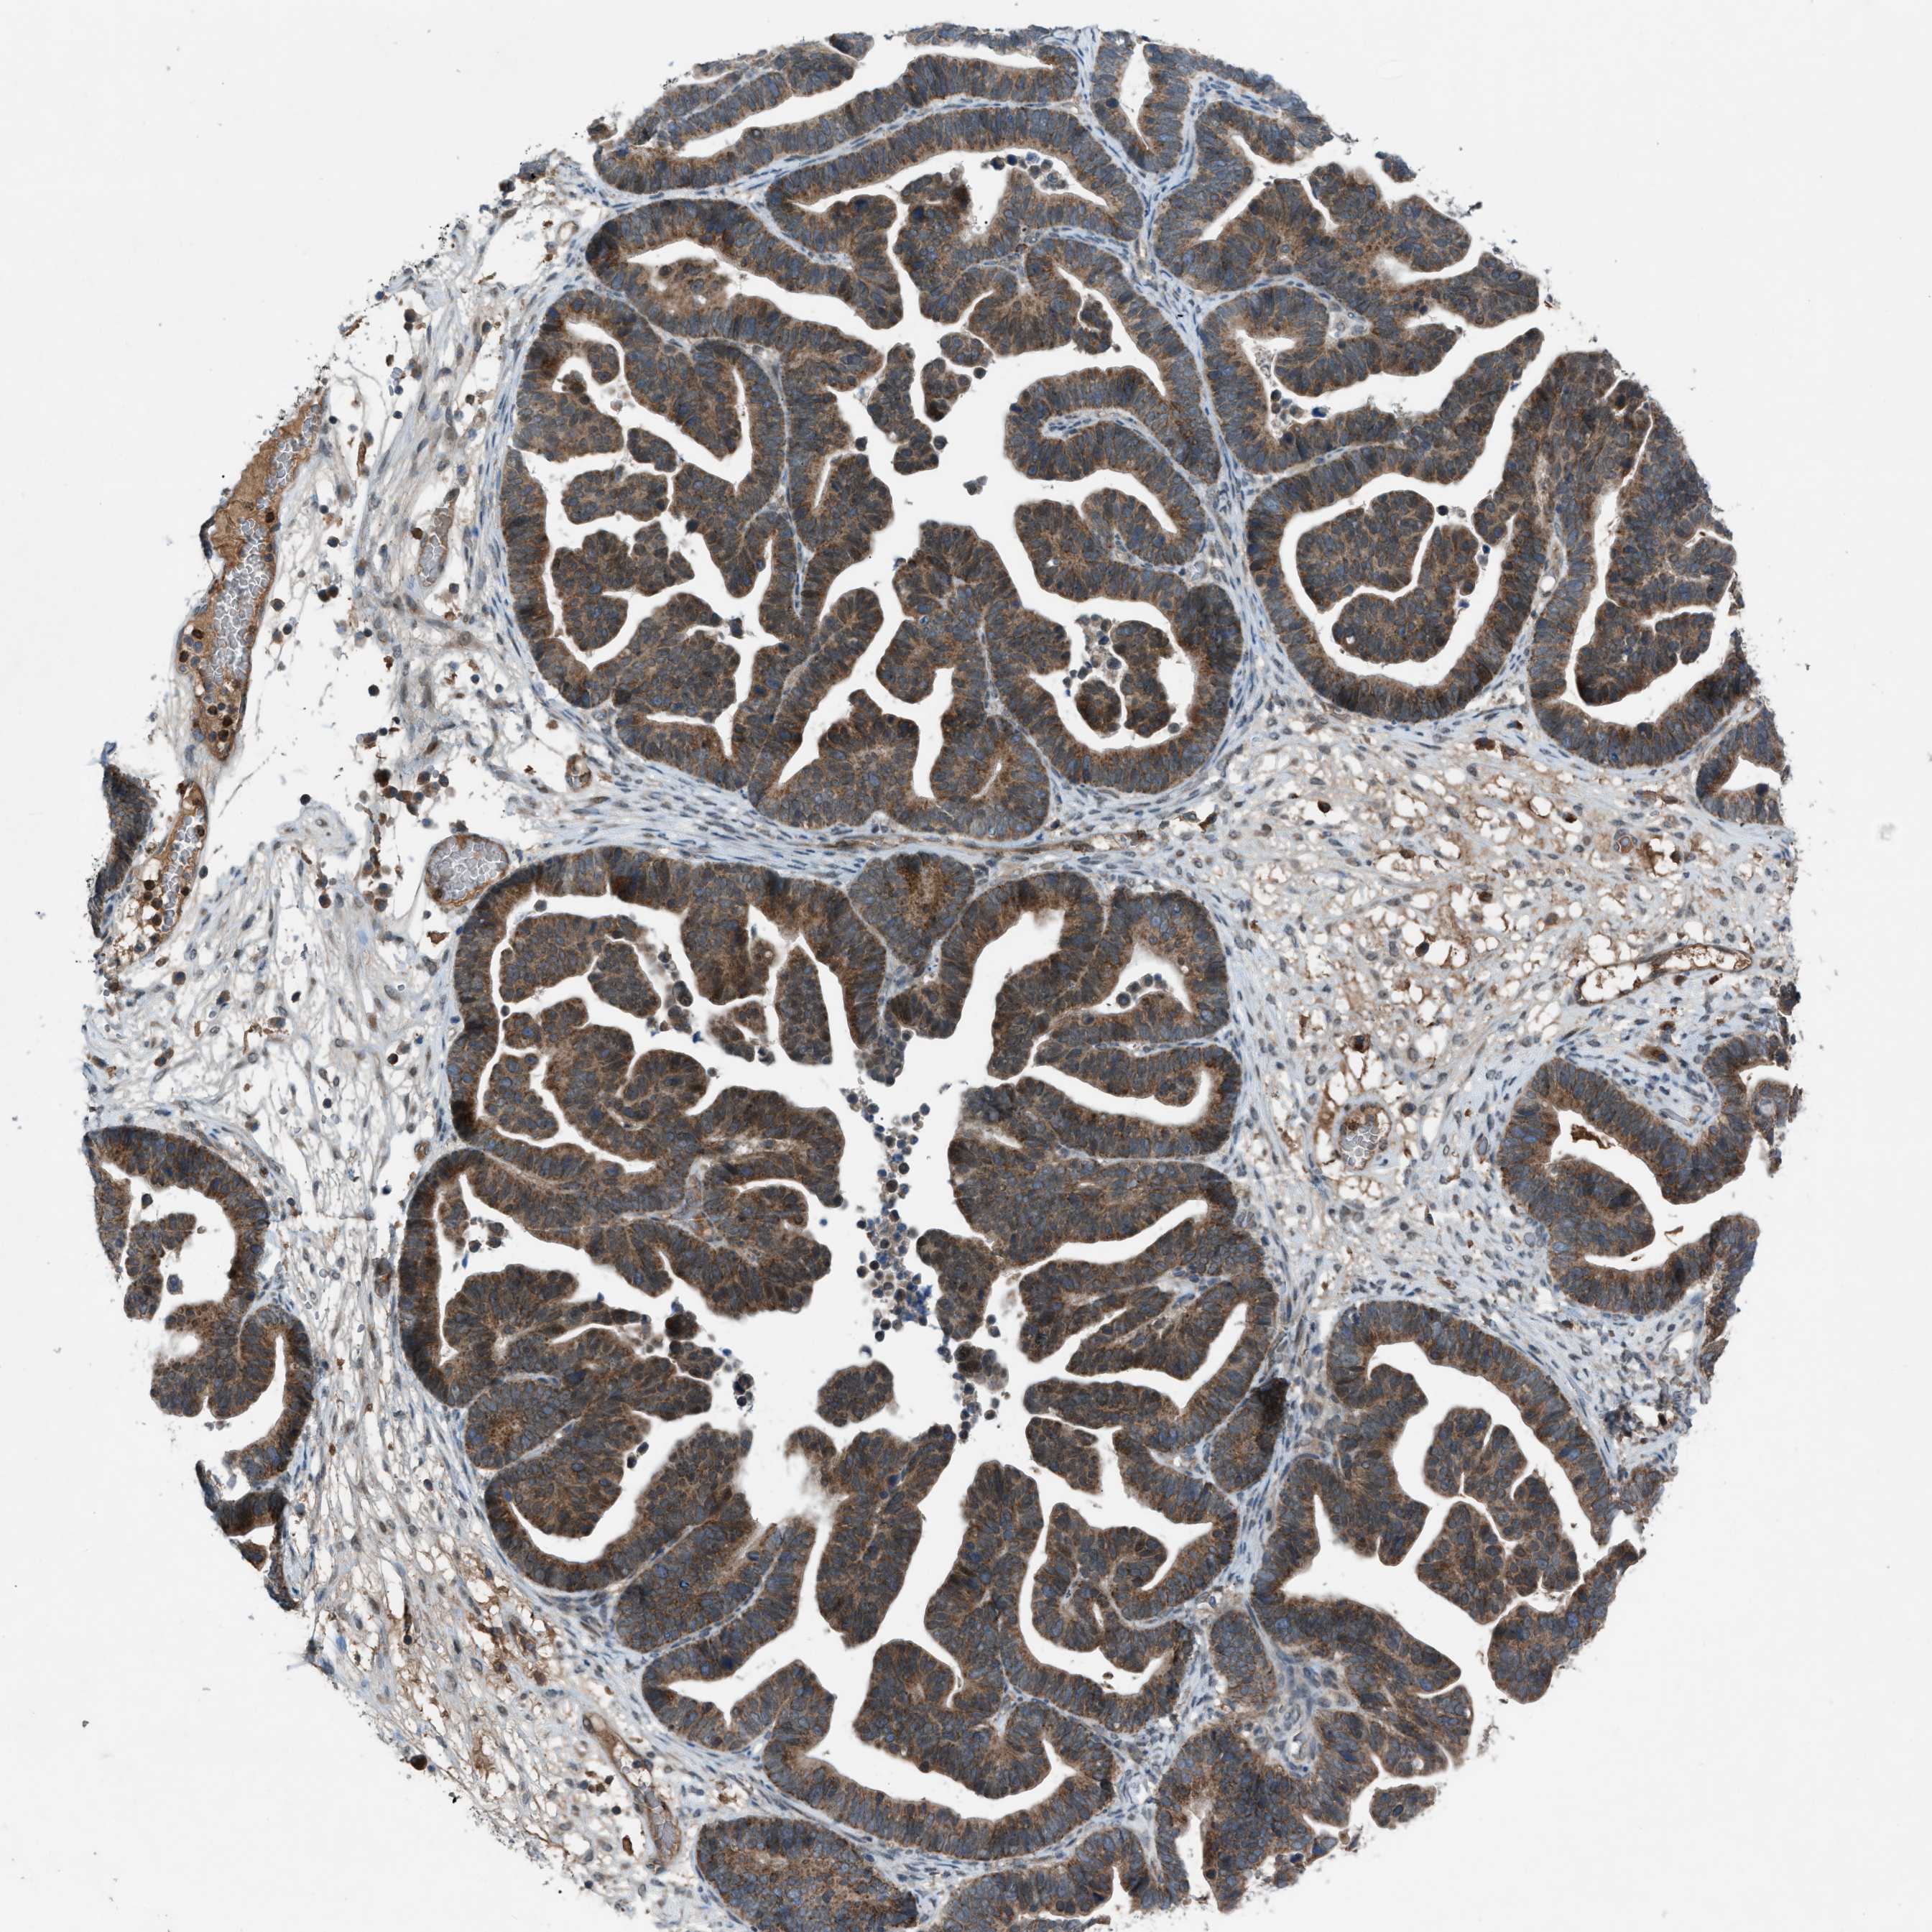

OVARIAN CANCER - Protein expressioni

A mouse-over function shows sample information and annotation data. Click on an image to view it in a full screen mode. Samples can be filtered based on level of antibody staining by selecting one or several of the following categories: high, medium, low and not detected. The assay and annotation is described here.

Note that samples used for immunohistochemistry by the Human Protein Atlas do not correspond to samples in the TCGA dataset.

Antibody stainingi

Antibody staining in the annotated cell types in the current human tissue is reported as not detected, low, medium, or high, based on conventional immunohistochemistry profiling in selected tissues. This score is based on the combination of the staining intensity and fraction of stained cells.

Each image is clickable and will lead to virtual microscopy that enables deeper exploration of all samples and also displays staining intensity scores, fraction scores and subcellular localization as well as patient and tissue information for each sample.

Antibody HPA015323

Antibody HPA015810

Carcinoma, endometroid

Cystadenocarcinoma, serous, NOS